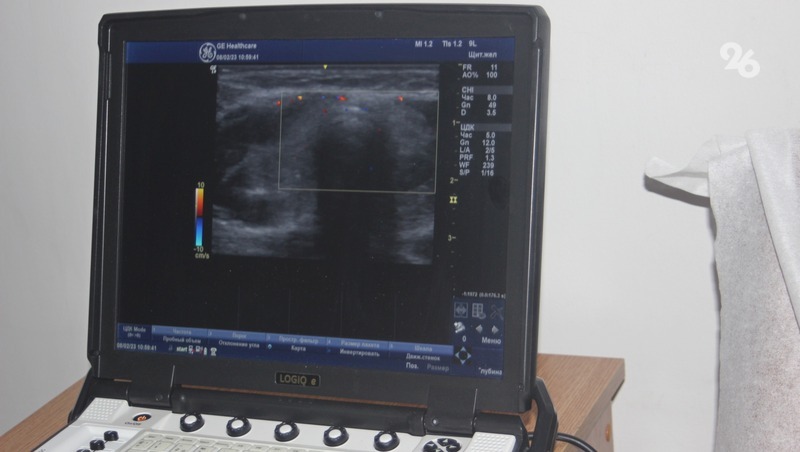

В диагностическом центре Невинномысска в эти дни работают более 20 врачей различных онкоспециальностей, они проводят медицинские осмотры работников промышленных предприятий города.

В рамках «Онкопатруля» в Невинномысске не только проводится медосмотр, но и мастер-классы, круглые столы для медицинского персонала первичного звена. На мастер-классах для врачей различных направлений рассматривают реальные случаи на примере пациентов, прошедших первичную диагностику при подготовке к мероприятиям.